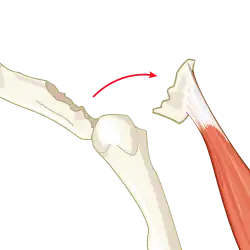

An avulsion fracture is a bone fracture which occurs when a fragment of bone tears away from the main mass of bone as a result of physical trauma. This can occur at the ligament by the application of forces external to the body (such as a fall or pull) or at the tendon by a muscular contraction that is stronger than the forces holding the bone together. Generally muscular avulsion is prevented by the neurological limitations placed on muscle contractions. Highly trained athletes can overcome this neurological inhibition of strength and produce a much greater force output capable of breaking or avulsing a bone.